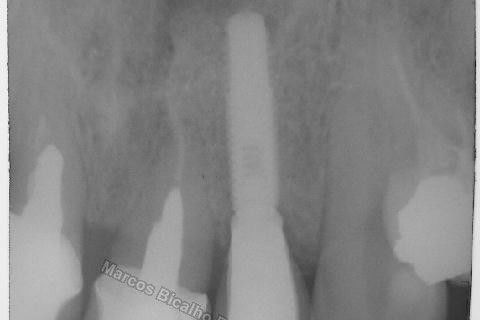

Este caso tem o objetivo de demonstração da técnica que normalmente sigo ; em casos onde ocorre fratura da raiz e consequentemente abscessos, com ou sem formação de fístula. Neste caso fiz a exodontia com preenchimento do alvéolo com biomaterial (osso bovino liofilizado + coágulo do paciente). Após 90 dias, mais ou menos, instalei o implante. Esperei mais 4 meses e realizei ontem (12/11/2010) a instalação do cicatrizador com o cuidado de preservar tecido mole, sem remoção de material, apenas afastando gengiva e "enrolando" a sobra de mucosa em direção a face vestibular, para promover conservação de papila futuramente. Se ocorrer excesso de papila, sem problema, remove-se um pouco, mas a intenção é não deixar faltar, o que resultaria em indicação para enxertos gengivais.

Fotos do caso